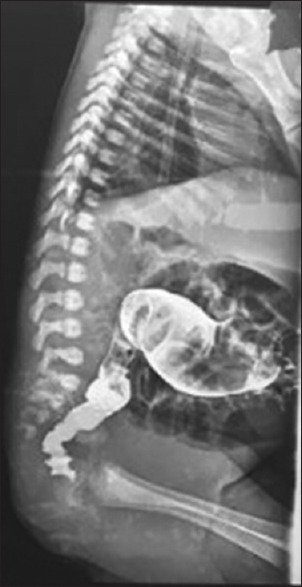

Results: Fifty two patients with a mean age of 18 months at the time of surgery. The male pre dominance was remarkable. The mean duration of the surgery was 2 h and a half hours. The surgical indication was based on the history, clinical findings and on the contrast enema (transition zone) with a 24 h film (prolonged contrast evacuation) and calculation of the rectosigmoid index (<1). With a mean follow up of 16 months, the morbidity was dominated by soiling, anastomotic strictures and enterocolitis. The mortality in one case was related to a post operative enterocolitis that was not amenable to resuscitation.